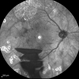

- Dengue Fever, rosacea conjunctivitis, preretinal hemorrhage

- Imaging device

- Fundus camera

- Fundus photograph of the left eye of a 32-year-old gentleman with dengue fever and thrombocytopenia. Photograph shows extensive retinal and pre-retinal haemorrhages, roth spots but no dengue retinitis. Same patient as in images 1-5.